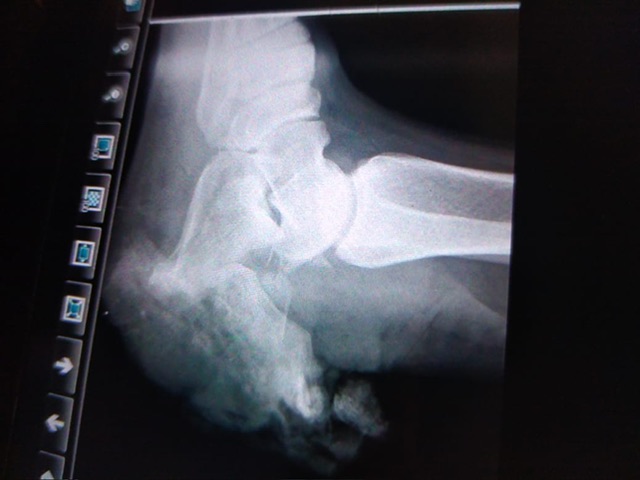

واستقبلت طوارئ مستشفى حورس التخصصي بأرمنت غرب مدينة الأقصر، ضحيتي حادثي الدهس، مصابين بتهتك في أنسجة الكاحل والعضلات مع قطع في الوتر وتفتت وكسور متعددة بالقدم والكاحل.

واتخذ الفريق الطبي لجراحة وتشوهات العظام بالتعاون مع فريق التجميل وجراحة الأوعية الدموية والتخدير والأشعة والمعمل بالمستشفى قرارهم بالتدخل الجراحي العاجل، والذي تطلب إجراء أكثر من 4 عمليات جراحة وتجميل على مدار ما يقرب من شهرين متتاليين لتثبيت عظام القدم والعصب، بالإضافة إلى عمليات بناء الأوتار والأوعية الدموية وكذلك معالجة بناء الأنسجة المحيطة، كما تم تثبيت الكسور وتغطية العظام برقع عضلية وجلدية.